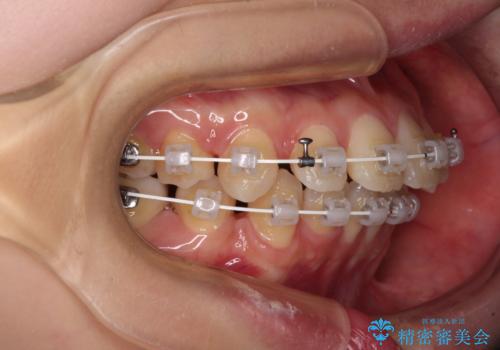

【モニター】口が閉じにくい 抜歯矯正で口元を引っ込める

- 前歯のデコボコや口元の突出感、口の閉じにくさを気にして来院された患者様です。

上下左右第一小臼歯4本を抜歯し、ワイヤー装置にてデコボコを解消しながら口元を引っ込めるよう矯正治療を行うこととしました。

抜歯スペースを閉じている過程で、左側の上下犬歯が引っかかってしまい、進捗が停滞しましたが、当初予定の2年~2年半の間で無事に治療を終えることができました。